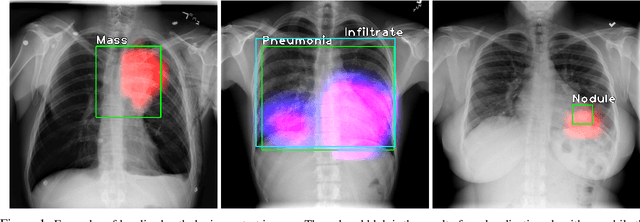

Abstract:Localization of an object within an image is a common task in medical imaging. Learning to localize or detect objects typically requires the collection of data which has been labelled with bounding boxes or similar annotations, which can be very time consuming and expensive. A technique which could perform such learning with much less annotation would, therefore, be quite valuable. We present such a technique for localization with limited annotation, in which the number of images with bounding boxes can be a small fraction of the total dataset (e.g. less than 1%); all other images only possess a whole image label and no bounding box. We propose a novel loss function for tackling this problem; the loss is a continuous relaxation of a well-defined discrete formulation of weakly supervised learning and is numerically well-posed. Furthermore, we propose a new architecture which accounts for both patch dependence and shift-invariance, through the inclusion of CRF layers and anti-aliasing filters, respectively. We apply our technique to the localization of thoracic diseases in chest X-ray images and demonstrate state-of-the-art localization performance on the ChestX-ray14 dataset.